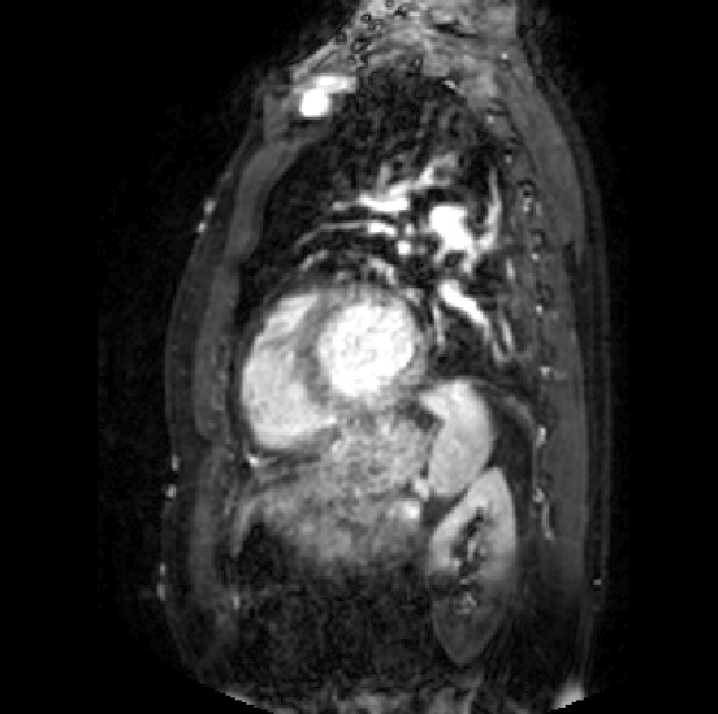

Table 7: Slice description generated by different multimodal LLMs (Blue: accurate description; red: inaccurate).

Samples (a) [Uncaptioned image] (b) [Uncaptioned image]

GPT-4Vision [18] This image is a sagittal CT scan of the human brain, providing a detailed view of the cranial structures. The cerebral cortex with its characteristic folds is clearly visible, along with the midline structures such as the corpus callosum and brainstem. The ventricles, which are fluid-filled spaces, appear as darker areas. The bright white outline represents the skull, which encases the brain. This type of scan is crucial for assessing brain abnormalities, injuries, or diseases, as it allows for a comprehensive evaluation of the brain’s anatomy and potential pathologies. This CT scan image shows an axial view of the abdomen, highlighting various internal structures. The large organ on the left side is the liver, appearing in a homogeneous gray tone. Adjacent to it, on the right, is the spleen, which is smaller and similarly shaded. The vertebral column is visible at the bottom center, appearing as a white circular structure. Surrounding tissues and organs, including portions of the intestines, are also visible, providing a detailed view of the abdominal cavity. This type of scan is essential for diagnosing abdominal conditions and assessing organ health.

Claude 3 [77] The image appears to be a medical scan, likely a CT or MRI, showing a cross-sectional view of a human brain. The brain structures are visible in shades of gray, with different densities represented. The scan appears to be focused on a specific region of the brain, revealing intricate details of the anatomy. Medical professionals would use this type of image to analyze the brain’s structure and identify any potential abnormalities or pathologies that may require further examination or treatment. This medical image appears to be a cross-sectional computed tomography (CT) scan of the abdomen. The image shows a detailed view of the internal structures, including the liver, spleen, and other abdominal organs. The high-contrast, black and white image provides a comprehensive representation of the anatomical features, allowing for the identification and examination of various organs and tissues. This type of imaging is commonly used in medical diagnosis and treatment planning for conditions affecting the abdominal region.

HuatuoGPT-Vision-7B [78] The image shows a sagittal view of the brain, which appears to be normal in structure and anatomy. The cerebral cortex, ventricles, cerebellum, and other key structures are clearly visible without any obvious abnormalities or pathological findings. This suggests that this is likely an unremarkable CT scan of the head taken after some form of treatment or intervention, as indicated by the reference information provided. The image shows a computed tomography (CT) scan of the abdomen, which reveals an enlarged liver with multiple hypodense lesions throughout both lobes. These findings are consistent with metastatic disease involving the liver parenchyma and peritoneal surfaces. The CT scan provides detailed anatomical information that can be used to assess the extent and distribution of the hepatic lesions for further clinical evaluation and management.